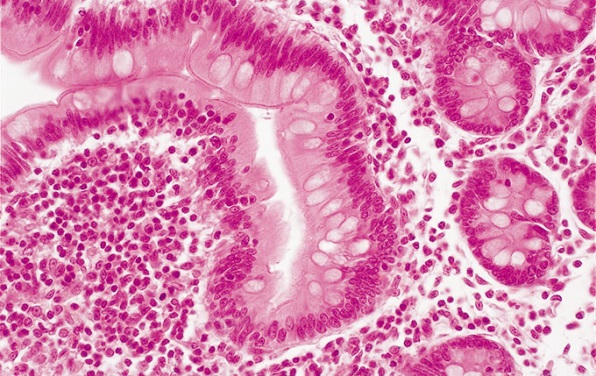

明场

明场聚光镜支持4×至100×成像,并且可以与CX-AL附件透镜配套使用,阻挡杂散光,在整个倍率范围内提供明亮的柯勒照明。